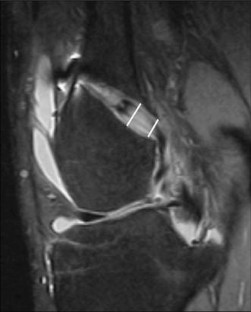

Tunnel enlargement after anterior cruciate ligament (ACL) reconstruction may compromise revision surgery. The cause of this tunnel enlargement is not yet fully understood, but it is thought to be multifactorial, with biomechanical and biological factors playing a role. Tunnel enlargement has been described particularly in patients who underwent ACL reconstruction with hamstring tendons with extracortical fixation devices. The purpose of our study was to evaluate prospectively with magnetic resonance imaging (MRI) the changes in femoral tunnel diameter following arthroscopic anatomic ACL reconstruction with hamstring tendons. At 3-month post-op, all tunnels had enlarged compared to the diameter of the drill and most tunnels enlarged more in the midsection than at the aperture. In the posterolateral tunnels, the entrance increased 16% in diameter and the middle of the tunnel increased 30% in diameter. In the anteromedial femoral tunnels, the tunnels enlarged 14% at the aperture and 35% in the midsection. All femoral tunnels enlarged and most of them enlarged in a fusiform manner. The biological factors explain better our findings than the mechanical theory, although mechanical factors may play a role and the cortical bone at the entrance of the tunnel may modify the way tunnels respond to mechanical stress.

Fig. 1